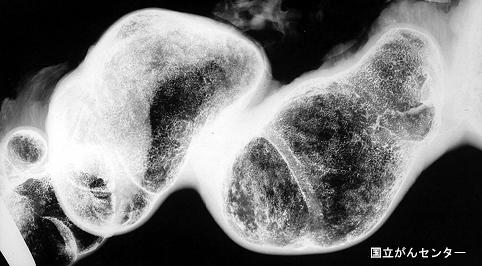

항결핵제의 투여에서 병리조직학적으로는 확진을 얻을 수 없었던 소장결핵

염증성 및 궤양성질환/결핵

소장/회장

X-P